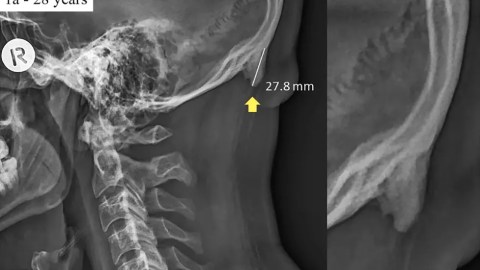

In a paper published earlier this year in Scientific Reports, they observed hornlike spikes growing in the back of people’s skulls that are 10-31mm in length. Shahar notes that bone spurs are considered large if they measure 3-5mm in length. The problem, he continues, is not necessarily the spurs, but the havoc they wreak in the person’s skeletal system.

Three years ago, Shahar and Sayers noticed a troublesome sight in neck X-rays. Enthesophytes, bone spurs protruding from the base of the skull—you can feel them if you check—were appearing in younger patients. Previously seniors that had suffered a lifetime of strain comprised the population for this problem. The team’s first paper, published in 2016, noted that 41 percent of young adults studied (out of 218 X-rays) had noticeable bone growth.

In their latest paper, Shahar and Sayers note that 33 percent of the population (out of 1,200 X-rays) now exhibits enthesophytes. This postural deformity results in chronic headaches and upper back and neck pain.